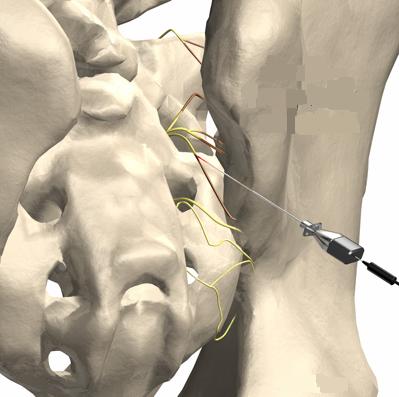

Exemplo dos pontos a serem denervados e anatomia da emergência dos nervos sacrais posteriores de S1 a S3.

Ao lado, modelo anatômico exemplificando os forames de S1 a S3, onde emergem os nervos responsáveis pela sensibilidade dolorosa da articulação sacro-ilíaca.

Ilustração mostrando a emergência dos nervos sacrais posteriores e a cânula de Rizotomia.